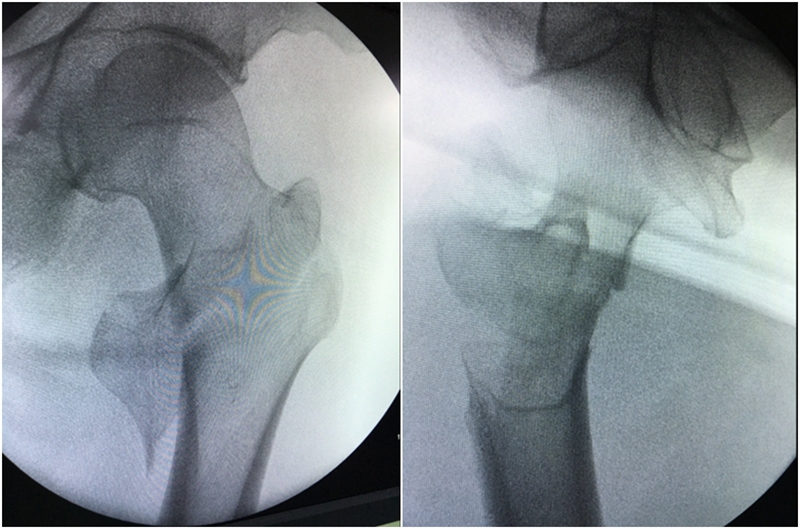

图3、图4 典型病例手法牵引复位后C-B塌示有过牵经调整后打入导针

(3)C-B验证后内收患肢,患肢内收伸直位(内收10°)髋屈曲15°,健侧肢体外展;

(1)仰卧,患肢外展外旋牵引复位,复位后将患肢内旋10-15°固定:C-B检测。

(2)复位标准:

正位:Shenton's线恢复;大粗隆尖端与股头中心在同一平面。

侧位:股干、颈、头的中心排成一条直线;